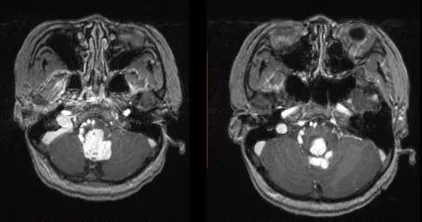

术中影像

术中DSA

术中栓塞前后结果比较

Y字形剪开硬膜,翻向上方及两侧,打开枕骨大孔处蛛网膜,即可暴露肿瘤。吸除栓塞后的少量血肿,并从下方抬起病灶,小心逐根电凝离断病灶供血动脉,一一剪断。避开引流静脉,分别从右侧,上方及左侧反复电凝并离断病灶供血动脉。病灶张力逐渐下降,引流静脉颜色变暗。

肿瘤深部累及四脑室底部及延髓,予以小心保护。最终离断引流静脉后,将病灶完整切除。进一步探查迂曲的引流静脉,未见明显出血。术野严格止血后关颅,硬膜修补缝合,骨瓣还纳,逐层缝合肌肉及皮肤。术中出血约500ml。